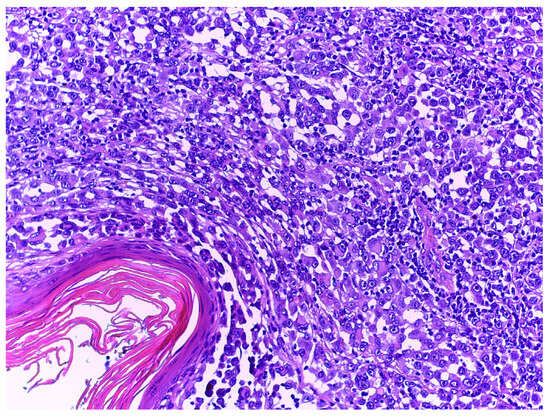

- Ronchi, A.; Cazzato, G.; Ingravallo, G.; D’Abbronzo, G.; Argenziano, G.; Moscarella, E.; Brancaccio, G.; Franco, R. PRAME Is an Effective Tool for the Diagnosis of Nevus-Associated Cutaneous Melanoma. Cancers 2024, 16, 278. [Google Scholar] [CrossRef] [PubMed]